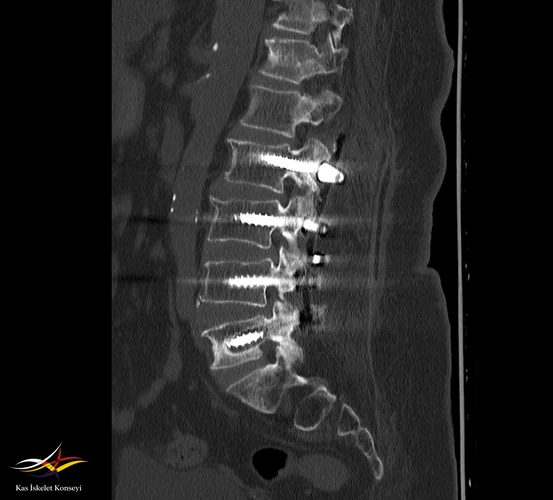

Resim 1. BT tetkikinde L5 pedikül vidalarında gevşeme bulguları (halo) saptanmıştır.